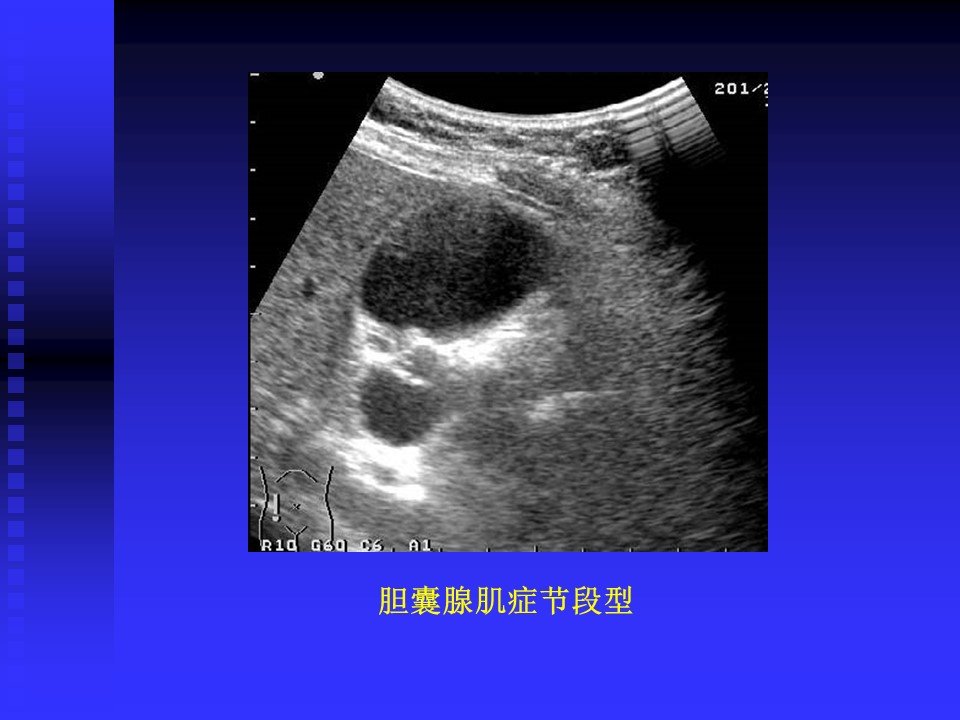

“胆道系统疾病超声诊断PPT” 的相关文章